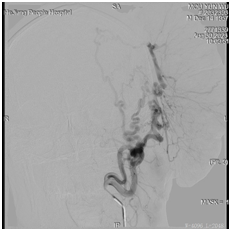

不幸的是,术前头颅DSA检查提示肿瘤血供异常丰富,双侧增粗颞浅动脉及枕动脉持续供血,手术中大出血可能性极大,并且患者肿瘤存在坏死感染,一旦破坏供血动脉,大出血死亡的可能性也很大,手术显然已刻不容缓。 由于肿瘤巨大,体位摆放成为摆在神经外科医务人员面前的一道难题,同时术中控制出血亦成为医务人员面前的拦路虎。尽管困难重重,经全科讨论,仍然决定进行肿瘤切除术,还患者一个正常的头颅。 果不其然,手术一开始,肿瘤供血动脉砰砰的搏动,肿瘤出血异常凶猛,并且肿瘤与头颅粘连紧密,分离非常困难。侯黎明主任和汪棋笙首先分离结扎供血动脉减少出血,循序渐进、层层分离,最终,在麻醉科的密切配合之下,巨大肿瘤得以全部切除。 术后的老牟次日就可以下床活动了,他说:“我感觉脑壳至少轻了10斤”。 神经外科主任侯黎明说,头皮肿物常见,但如此巨大的头皮肿物实属罕见,下一步我们要为创口进行皮肤移植,为老牟恢复容貌。